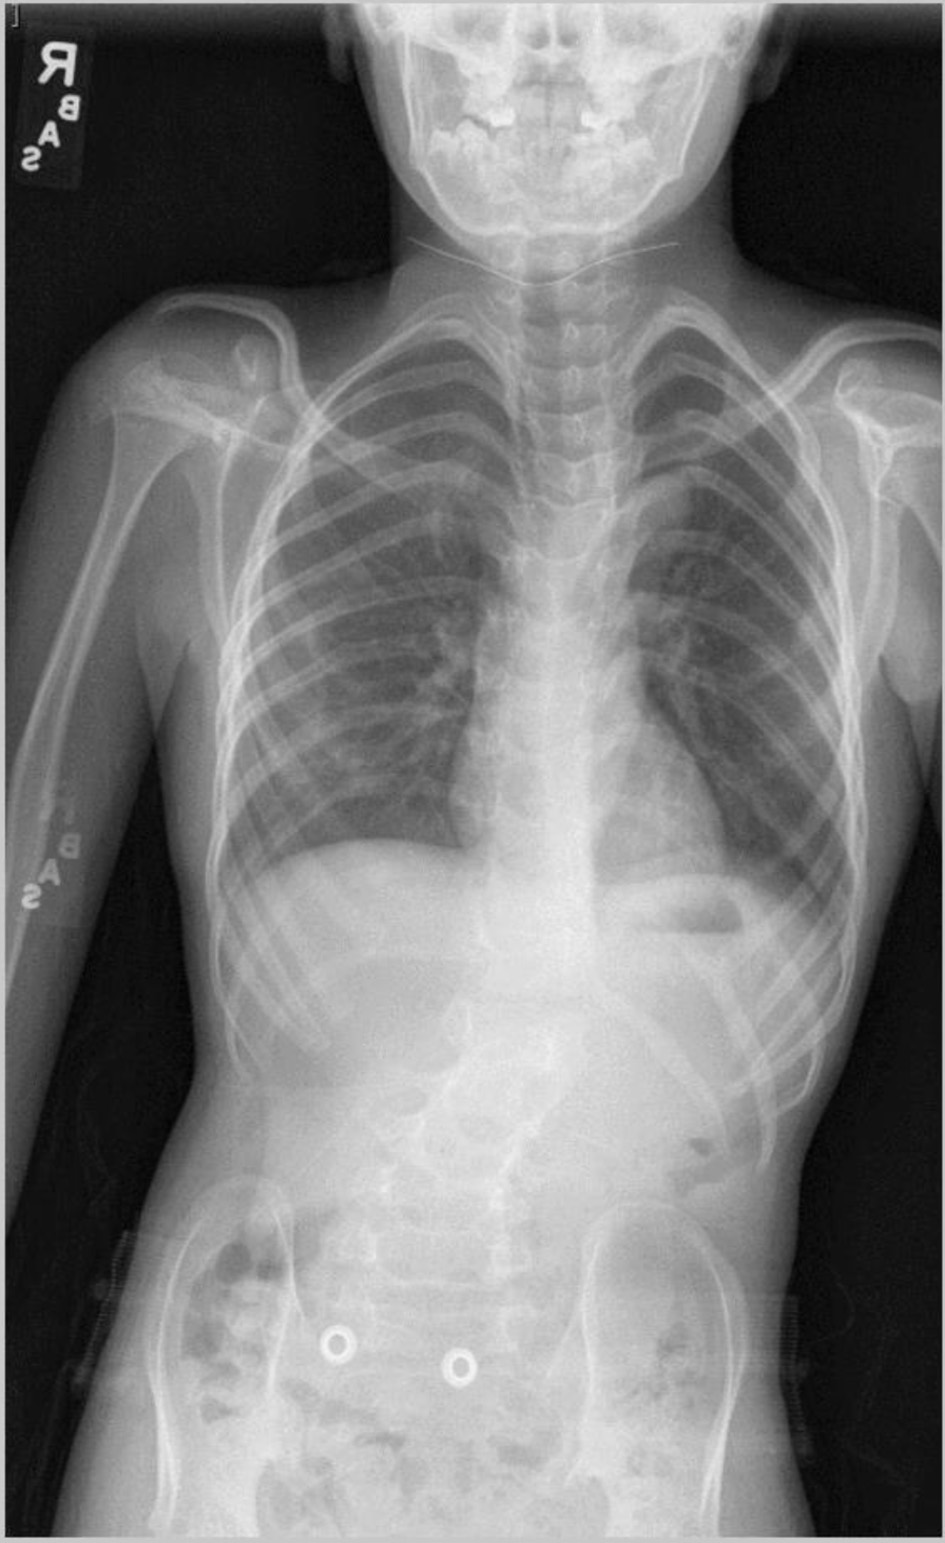

Review of this case and presentation in this format followed the guidelines of the Institutional Review Board of Nationwide Children’s Hospital. The study was conducted in compliance with the ethical standards of the responsible institution on human subjects as well as with the Helsinki Declaration. The patient was an 11-year, 2-month-old, 24.2 kg male presenting for a PSF with instrumentation from T11-L3 to treat scoliosis. The diagnosis of Beals syndrome was initially confirmed during his early childhood in China, but as he was adopted, specific information was lacking. At 6 years of age, he came to the United States and the diagnosis was confirmed based on the physical exam and radiographic findings. Physical findings included a right paraspinal prominence when bending forward and a lumbar moderate left-sided paraspinal prominence with a kyphotic component. His fingers had significant clinodactyly and camptodactyly. His feet were long and slender. Along with a severe 63° kyphoscoliosis, spinal imaging showed a hypoplastic L1 vertebral body with short pedicles partnered with degenerative changes of the L1/L2 disc (Fig. 1). Other comorbid conditions included a dilated aortic root, post traumatic stress disorder, and multiple contractures of the upper and lower extremities bilaterally. An echocardiogram noted the aortic root be severely dilated with trivial aortic valve regurgitation, moderate dilation of the ascending aorta, and normal biventricular size and systolic function (Fig. 2). He had a history of two previous anesthetic events for general anesthesia during magnetic resonance (MR) imaging with reports of emergence delirium. Additionally, during the second MR under general anesthesia, neck flexion resulted in airway obstruction despite the presence of an oral airway. This led to the decision to place an air-Q size 1.5 laryngeal mask airway (LMA) which allowed neck flexion for imaging without airway obstruction. Current medications included losartan (12.5 mg twice a day) for blood pressure management related to aortic root dilatation and cetirizine (5 mg once a day) as an anti-histamine for season allergies. Preoperative physical examination revealed a Mallampati Class II airway with normal mouth opening. There was limitation of neck flexion and extension. Respiratory and cardiac examinations were unremarkable. Preoperative laboratory evaluation including coagulation function, complete blood count, electrolytes, blood urea nitrogen, and creatinine was within normal limits. The patient was held nil per os for 6 h and transported to the operating room where standard American Society of Anesthesiologists’ monitors were placed. Anesthesia was induced by the inhalation of incremental concentrations of sevoflurane in air and oxygen with the maintenance of spontaneous ventilation. A peripheral intravenous cannula (18 gauge) was placed. Once adequate bag-valve-mask ventilation was demonstrated, propofol (30 mg) and rocuronium (20 mg) were administered. The trachea was intubated with a 6.0 mm cuffed endotracheal tube (ETT) using indirect videolaryngoscopy with a Glidescope® laryngoscope. There was a grade I laryngoscope view with full view of the glottis. Following the induction of anesthesia and endotracheal intubation, a second peripheral intravenous cannula and an arterial cannula (radial artery) were placed. The patient was turned prone onto the operating room table and positioned with padding of pressure points. To facilitate neurophysiological monitoring per our usual clinical practice and intraoperative pathway, maintenance anesthesia included desflurane titrated to maintain the bispectral index at 50 - 60, a remimazolam infusion (5 - 15 µg/kg/min), methadone (1.2 mg) followed by a remifentanil infusion adjusted from 0.05 to 0.3 µg/kg/h to maintain the mean arterial pressure at 55 - 65 mm Hg, and lidocaine (1 mg/kg/h) [4]. Measures to limit intraoperative blood loss and the need for the administration of allogeneic blood included controlled hypotension, intraoperative cell salvage, and tranexamic acid (50 mg/kg bolus dosing followed by 5 mg/kg/h). Surgical site prophylaxis was provided by cefazolin (50 mg/kg) every 3 h. Dexamethasone (4 mg) and ondansetron (3 mg) were administered to prevent postoperative nausea and vomiting. There were no adverse intraoperative events. The total fluid intake was 1,500 mL including 250 mL of 5% albumin (250 mL) and 1,250 mL of Normosol®-R electrolyte solution. Intraoperative urine output was 825 mL and estimated blood loss was 50 mL. At the completion of the surgical procedure, residual neuromuscular blockade was reversed with sugammadex, the patient was turned supine, and his trachea extubated when he followed commands. Postoperative analgesia included hydromorphone delivered via a patient-controlled device, intravenous acetaminophen every 6 h, intravenous ketorolac every 6 h, and a lidocaine infusion (1 mg/kg/h for the initial 24 postoperative hours). The patient was transported to the post-anesthesia care unit and then admitted to the inpatient ward. No postoperative respiratory issues were noted. The postoperative course was uneventful, and he was discharged home on postoperative day 2.

Click for large image

Figure 1. Preoperative vertebral radiograph showing scoliosis.